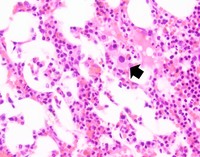

Atypical megakaryocytes

Many atypical megakaryocytes are seen characterized by small size, hypolobated or non-lobated nuclei, and often plasmacytoid appearance with eccentric nuclei. Erythropoiesis and granulopoiesis are relatively unremarkable. Blasts are not increased.